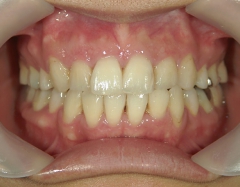

矯正歯科 治療後矯正歯科 全顎ワイヤー矯正 治療後矯正歯科(全顎ワイヤー矯正)治療後

矯正歯科 治療後

no.31_1962_治療後_右.JPGno.31_1962_治療後_正面.JPGno.31_1962_治療後_左.JPG